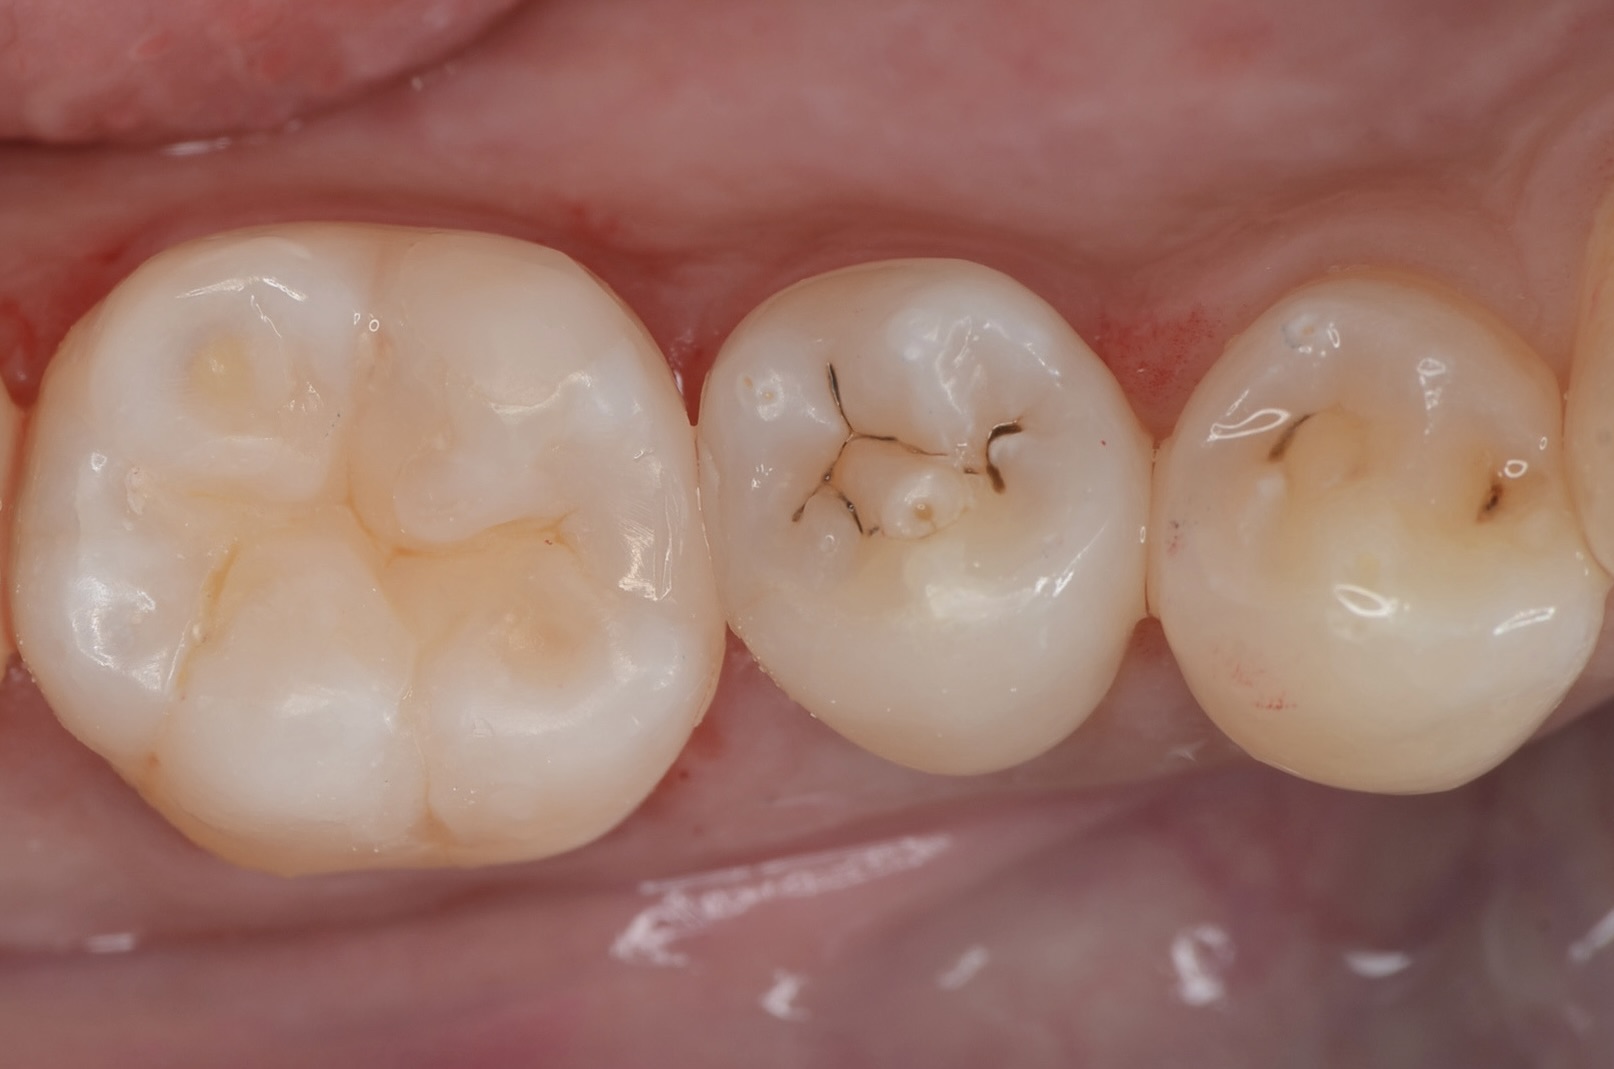

After

ダイレクトボンディング

天然歯の自然な形態を模倣してレジンを充填しました。 -